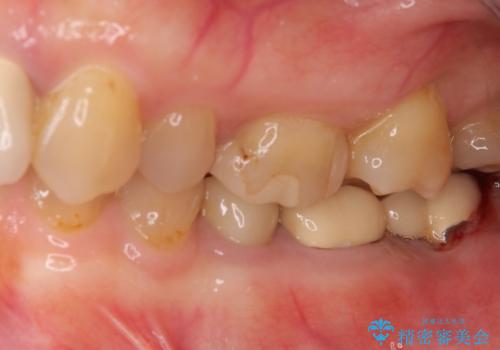

- 抜歯が必要と診断された奥歯の治療を希望して来院された患者様です。

一番奥の歯は歯根の一部を残した状態で、手前の歯とブリッジが装着されていました。

奥歯は歯根周辺の歯槽骨が広範囲に失われており、抜歯が必要と判断されました。

ブリッジの手前側の歯は、根管治療が必要な状態でした。

根管治療を行ったは、以前の治療で開けられて思われる穴が歯の内部に開けられており、炎症を起こしていました。

根管治療と合わせて、穴の開けられている部分を修復したところ、炎症による歯槽骨吸収に改善が見られました。

インプラント埋入にあたり、歯槽骨での炎症が広範囲であったことから、事前に骨造成を行いました。